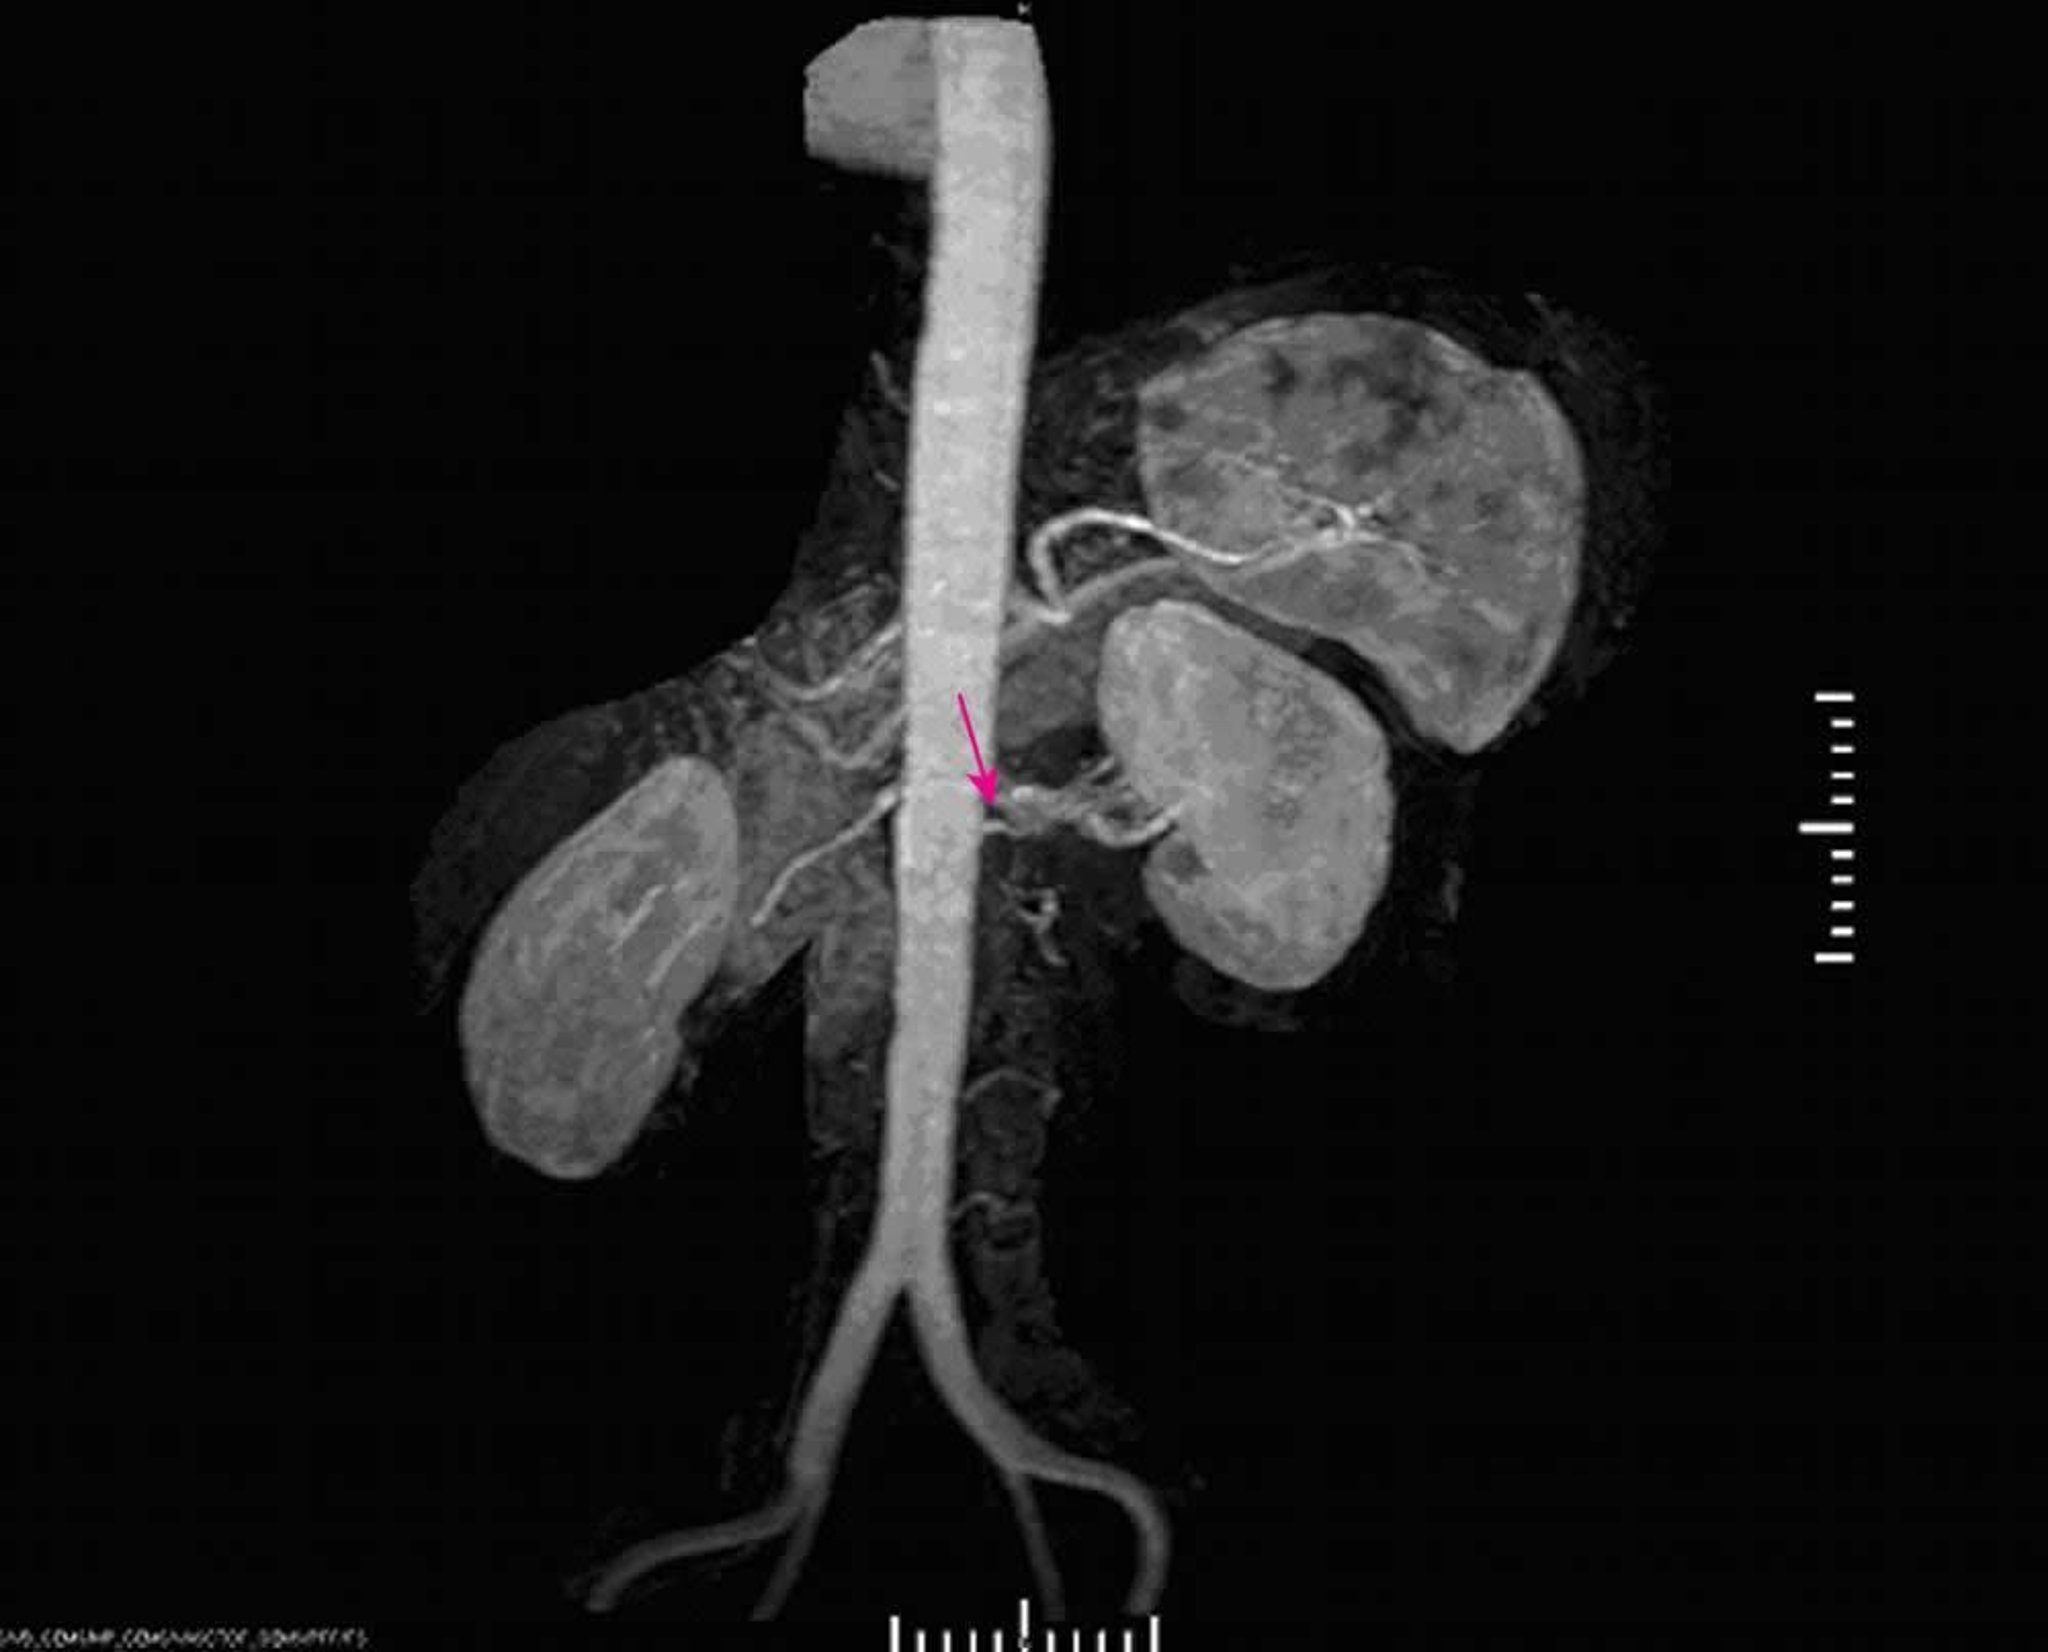

Hipertensión renovascular (angiografía por resonancia magnética)

La angiografía por resonancia magnética muestra una estenosis importante en el origen de la arteria renal izquierda.

Image provided by Jan N. Basile, MD.